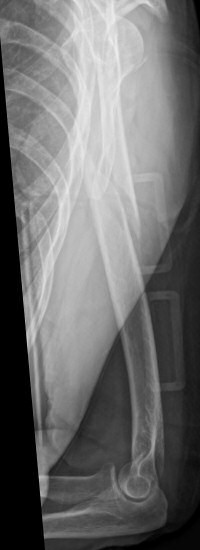

Exempel på humerusfraktur som behandlats icke-kirurgiskt, röntgenbilder efter 19, 40 resp. 71 dagar